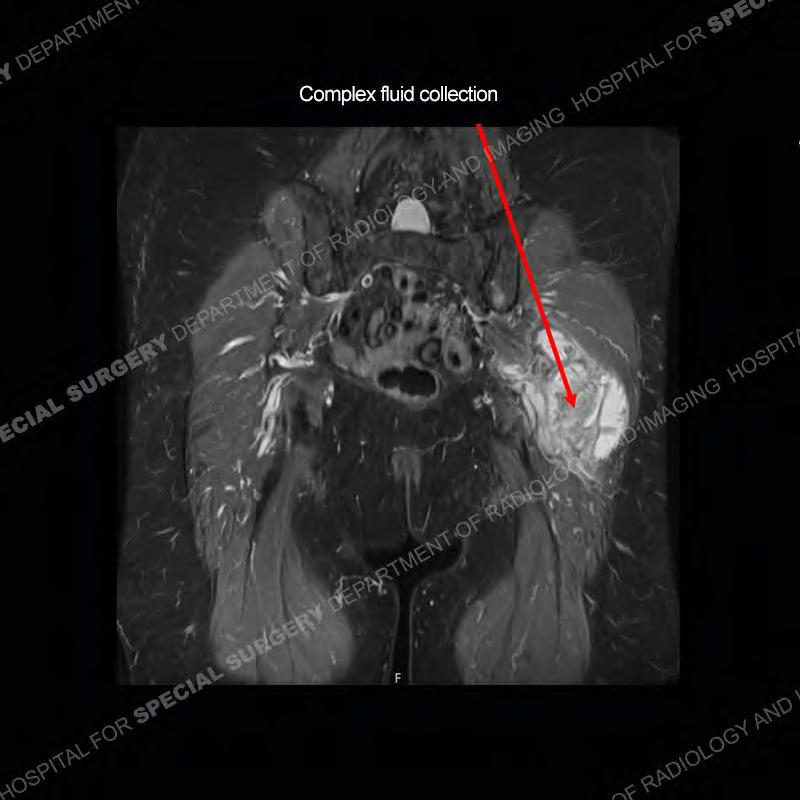

The radiograph is not particularly contributory in this case. The MRI demonstrates markedly abnormal architecture of the gluteus minimus and anterolateral band of the gluteus medius. Portions of the tendons are high signal, portions are highly attenuated, and portions are disrupted. A large, complex fluid collection is present in the adjacent soft tissue.

Diagnosis: Gluteal Tendinosis and Disruption with Complex Trochanteric Bursal Collection

The bursae about the greater trochanter can be a little bit confusing especially given the terminology. Trochanteric bursitis is implied to mean the subgluteus maximus bursa which is present deep to the maximus and just lateral/superficial to the trochanter. That is the bursa involved in this case. In this case the complexity of the bursa relates to the tendon tearing with inflammatory change and probably hemorrhage accounting for the complexity. Two other, less frequently involved bursa are also present. The subgluteus medius and subgluteus minimus bursa are found just deep to the named tendons. Although pathology does frequently follow the previously described pattern it is possible to have isolated pathology to either the medius or minimus.